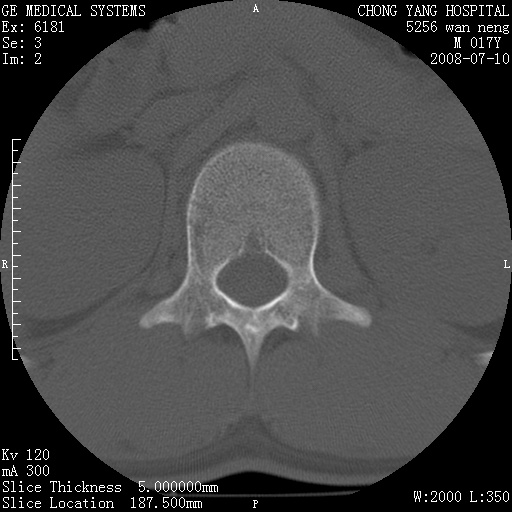

腰3、4椎弓崩裂

腰3、4椎弓不连

支持:腰3、4椎弓峡部崩裂。

腰3、4椎弓峡部不连

支持:腰3、4椎弓峡部崩解。

腰3、4,如受过外伤则为陈旧骨折,否则为骨质不连

图片漂亮,目前也只能看到腰3、4骨质不连

腰3、4椎弓峡部裂。

腰3、4椎弓峡部裂。支持

重建图像见多个椎弓峡部不连(不足为据),平扫未见异常。

支持腰3、4椎弓峡部崩裂。